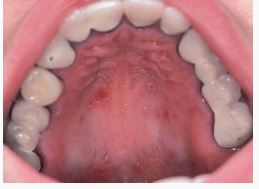

Suu ja hammaste ravi vastavalt vajadusele

Tõhustatud suuhaiguste ennetamine

Suu hügieen

•Hambaid tuleb igal hommikul ja õhtul põhjalikult pesta pehme hambaharjaga või elektrihambaharjaga. Unustada ei tohi hambavahesid.

•Lisaks fluori sisaldavale hambapastale on kasulik tarvitada ka mõnd lokaalset vahendit, eriti fluori sisaldavaid imemistablette või närimiskummi. Kaaries riskirühma patsientidele igapäevased suuloputused 0,05% NaF-lahusega.

•Vältida tuleb alkoholi sisaldavat suuvett.

•käima hambaarsti vastuvõtul tavalisest sagedamini, iga 3–6 kuu järel.